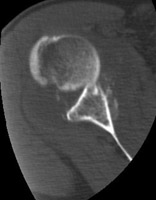

- Click on the image for a larger versionDAxial CT. This image demonstrates the anteriorly dislocated humeral head, the source of the Bankart fracture